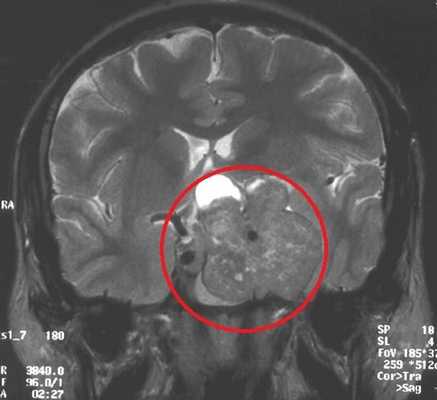

МРТ гипофиза. На МР-томограмме определяется гигантское образование неоднородной структуры (обведено) — макроаденома гипофиза.

Чаще всего исследование проводится для диагностирования аденомы гипофиза и определения ее величины: микроаденомы (до 10 мм), макроаденомы (10—30 мм) и гигантской аденомы (более 30 мм). Также с его помощью обнаруживаются неоднородности структуры, асимметрия границ, изменения положения воронки гипофиза и ее структуры, а также деформации окружающих костных тканей.